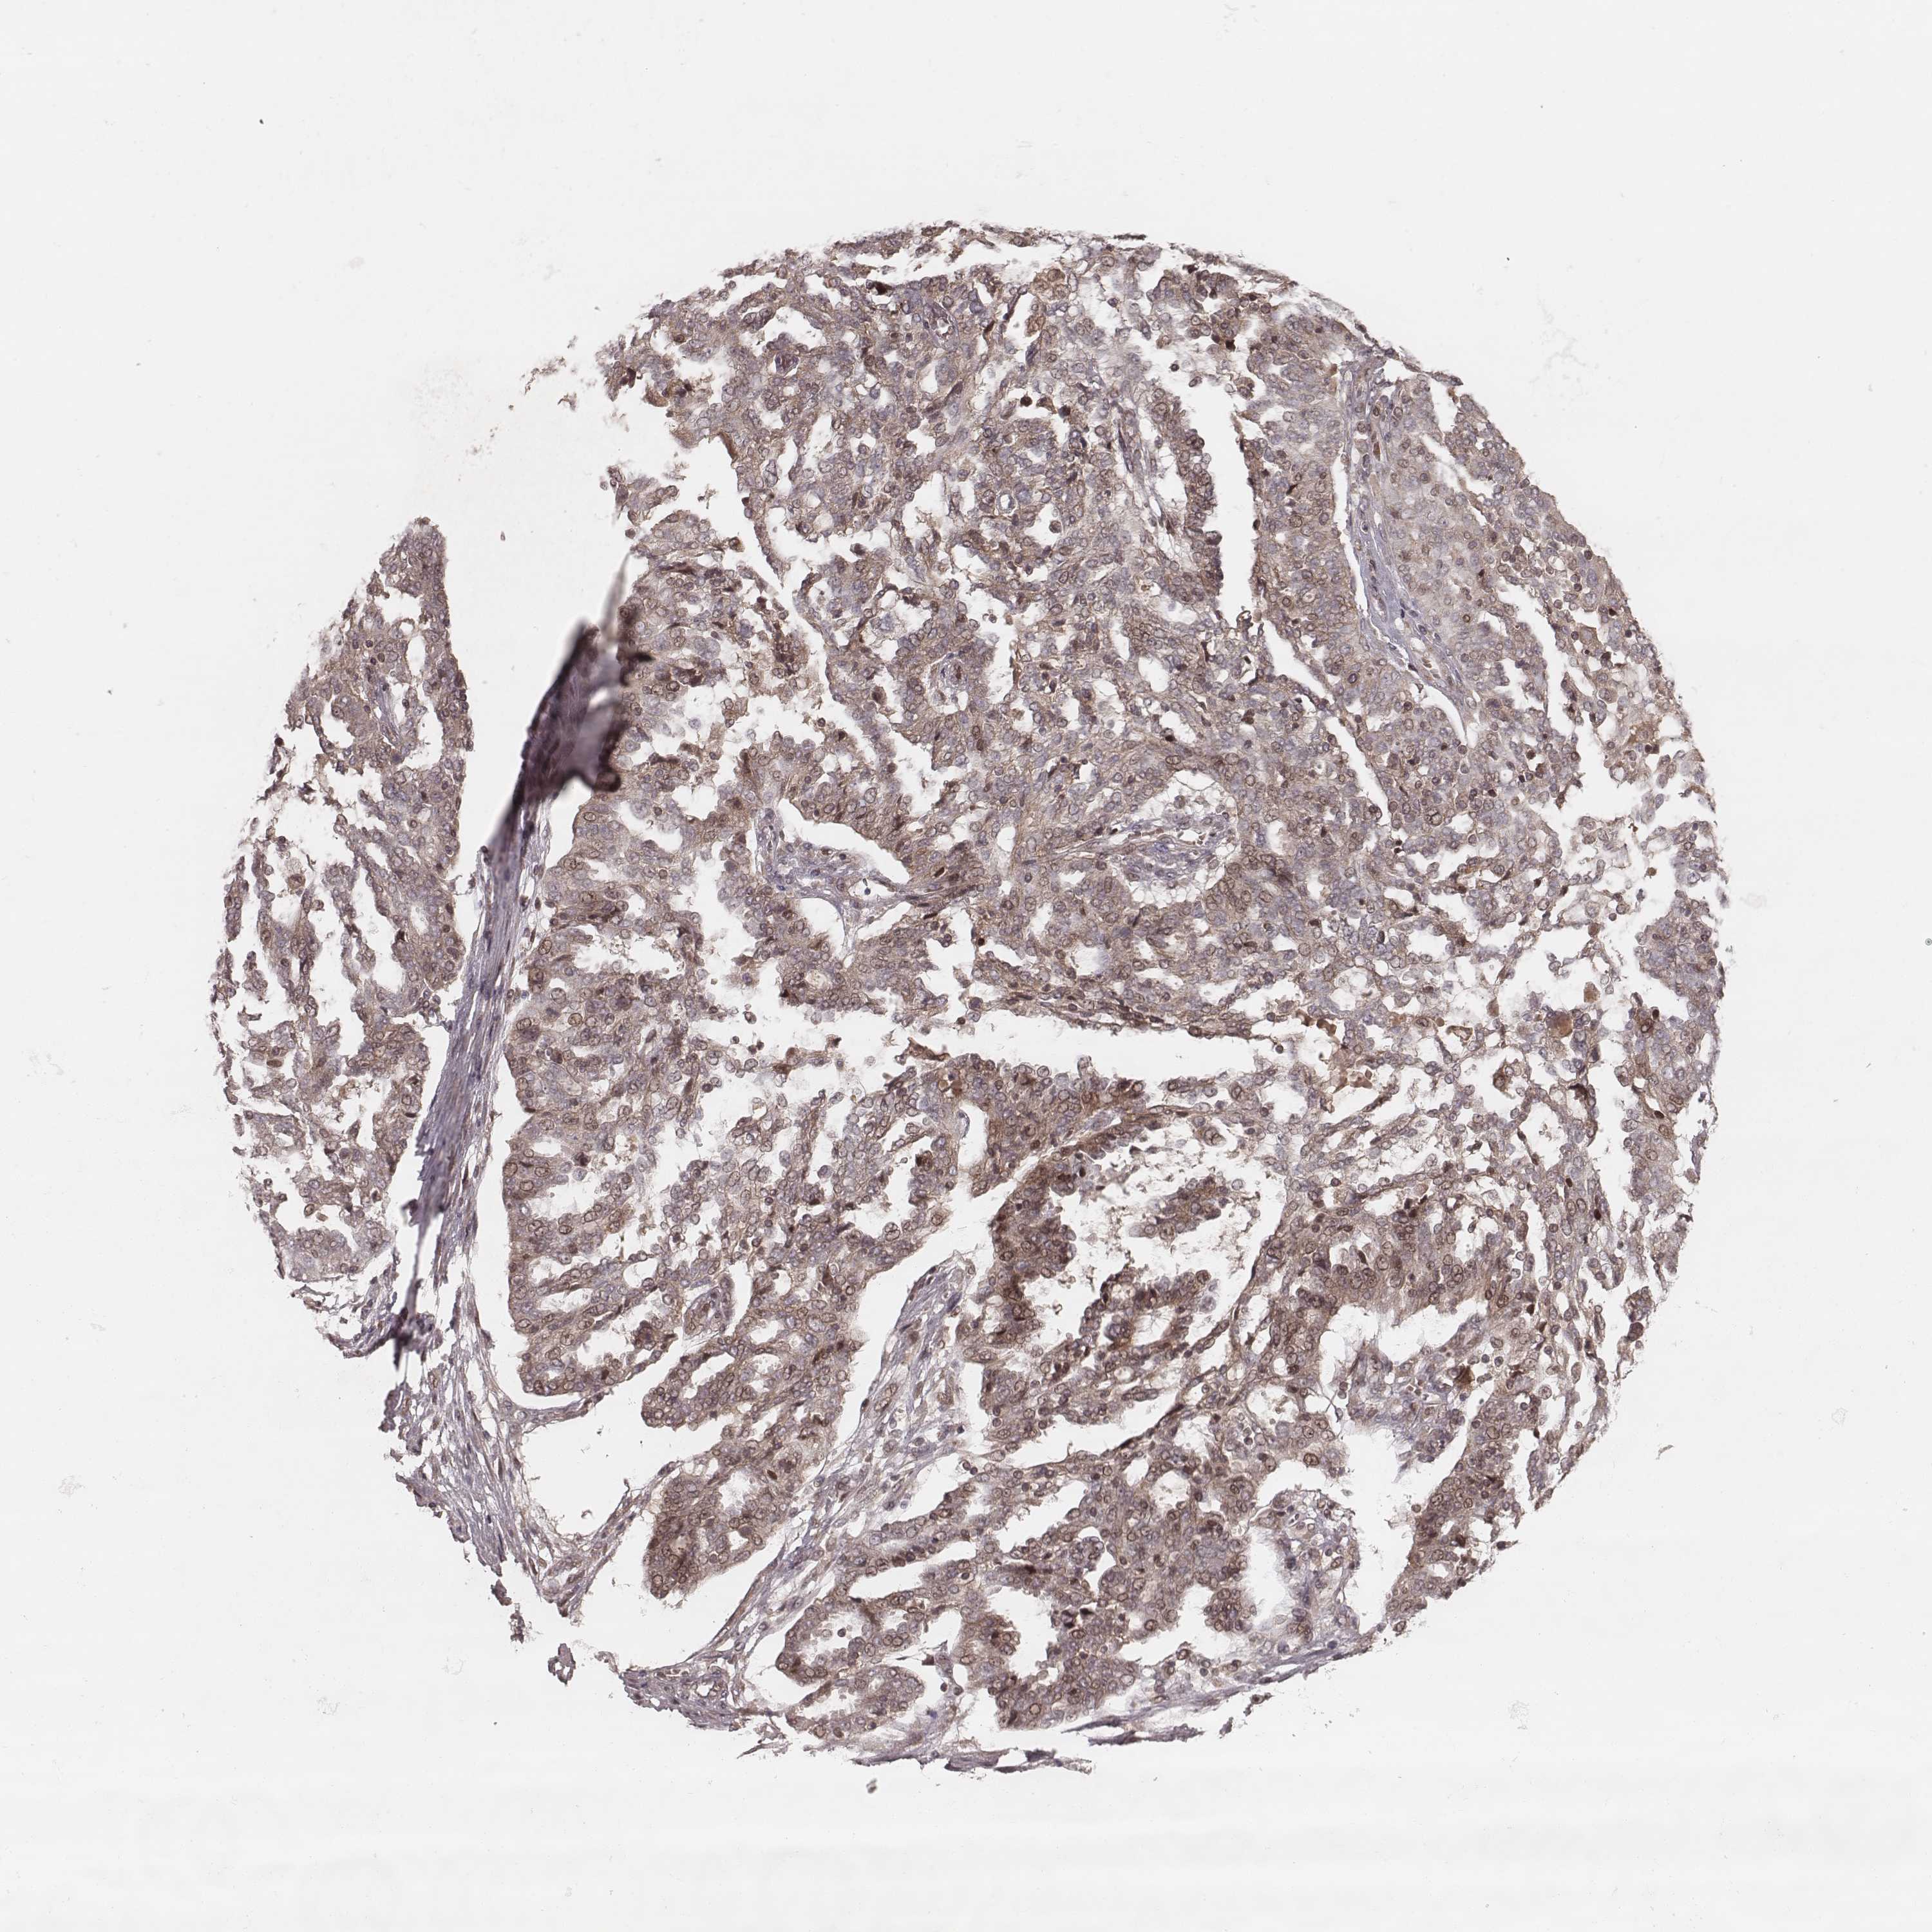

OVARIAN CANCER - Protein expressioni

A mouse-over function shows sample information and annotation data. Click on an image to view it in a full screen mode. Samples can be filtered based on level of antibody staining by selecting one or several of the following categories: high, medium, low and not detected. The assay and annotation is described here.

Note that samples used for immunohistochemistry by the Human Protein Atlas do not correspond to samples in the TCGA dataset.

Antibody stainingi

Antibody staining in the annotated cell types in the current human tissue is reported as not detected, low, medium, or high, based on conventional immunohistochemistry profiling in selected tissues. This score is based on the combination of the staining intensity and fraction of stained cells.

Each image is clickable and will lead to virtual microscopy that enables deeper exploration of all samples and also displays staining intensity scores, fraction scores and subcellular localization as well as patient and tissue information for each sample.

Antibody HPA059715

Staining

High

Medium

Low

Not detected

Intensity

Strong

Moderate

Weak

Negative

Quantity

>75%

75%-25%

<25%

None

Location

Nuclear

Cytoplasmic/membranous

Cytoplasmic/membranous,nuclear

Cystadenocarcinoma, serous, NOS

Cystadenocarcinoma, mucinous, NOS

Carcinoma, endometroid